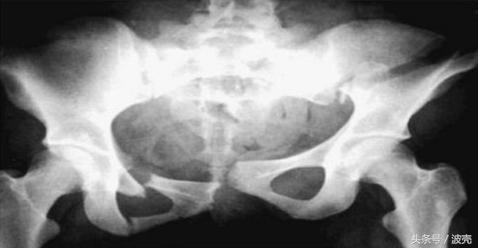

从生理学上来说,能否顺产主要取决于三个要素:产道、产力、胎儿,一个要素异常都会发生难产的现象,而女性骨盆狭小就属于产道的问题了。

骨盆是婴儿分娩时的必经之路,一旦狭小就容易卡住婴儿,难以分娩出来。而古代医疗手段不发达,为了让宝宝能从狭小的骨盆出来,接生婆一般会采取这两种方式:用蛮力拽出来、缩小宝宝面积。

但在南方地区就有点不同了。为了避免女性因为骨盆小不能生娃,把家族血脉给断掉,所以在女宝宝生下来被判断骨盆可能狭小的情况下,会把女婴的骨盆给折断。

这种折断损伤不可逆,无法自我治愈,最终让骨盆变得松弛,避免日后难产的几率。所以当时社会的女性走路起来松松垮垮的,非常难看,这是因为她们的骨盆被折断了。